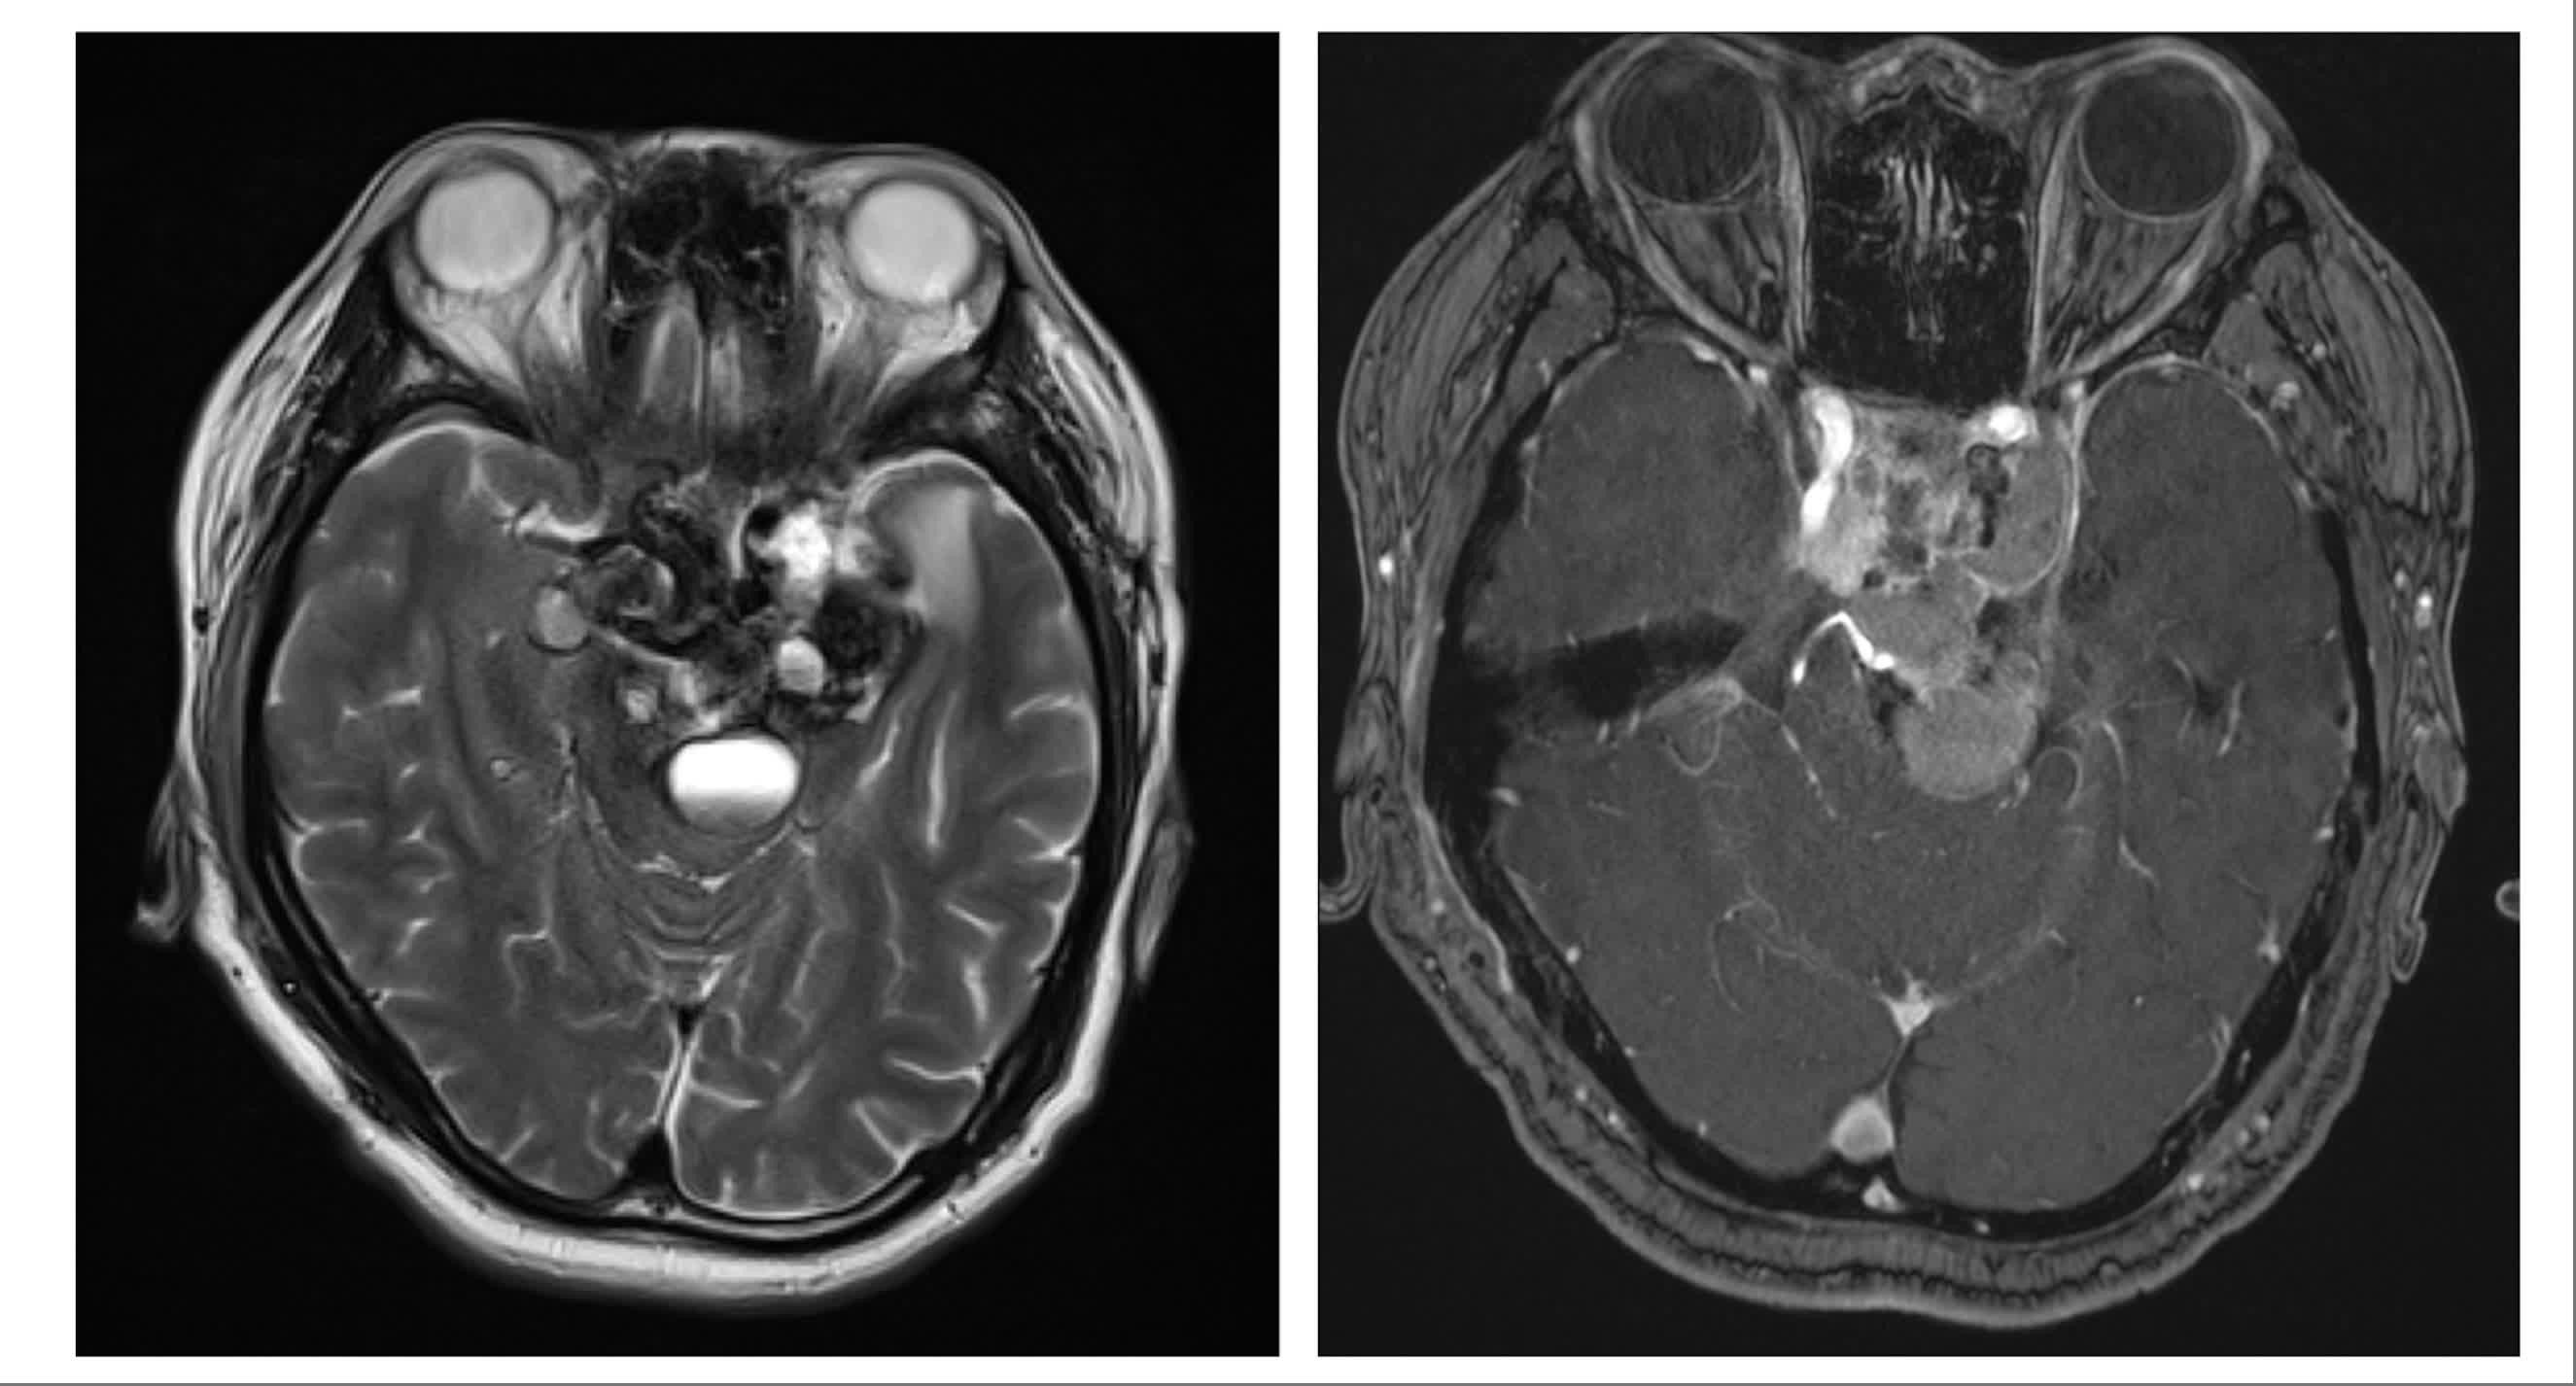

此外,顱底內窺鏡經眶手術還可用於術前診斷。麥凱鈞舉例說明,部分患者的顱底腫瘤位置狹窄,直徑僅約1厘米甚至數毫米,常規核磁共振(MRI)難以清晰顯示,此時需要提取腫瘤組織進行病理化驗。應用經眼眶手術後,團隊無需開顱,即可直接經眼眶精準取樣。他分享:「我有幾位患者通過這種方式取得組織,結果出乎意料——可以通過藥物等非手術方式治療。這對患者而言無疑是更好的選擇,因為無需再承受第二次手術。」